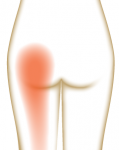

·原因: 疼痛大约在屁股摺痕处。尤其是在你膝盖伸直且将身体向前弯腰时,症状会更明显。这种型态的疼痛表示是连接到骨盆的腘绳肌肌腱受伤,这通常是因为过度的拉扯腘绳肌。(如在瑜伽中:当瑜伽练习者需要保持双腿笔直向前弯曲,然后强迫自己摆姿势时,可能最终会损伤肌腱。)当我们的肌腱受伤,腘绳肌会自然的收缩,试图去保护受伤的肌腱。然而我们认为的是:"腘绳肌紧绷又疼痛,要去伸展它,疼痛自然会消失了",而这样的方式却无法让肌腱修复,反而是重复使其受伤——过度伸展然后再受伤,这样的循环会使复原时间变更长。较好的方式是借由适当地收缩腘绳肌来增加受伤区域的循环,如果可以的话,做简单轻微的伸展。当疼痛急性期结束后,你可以慢慢增加伸展的角度。您的朋友或患者中,是否有人向你这样抱怨过:我的髋部在走路、睡觉时会痛,物理治疗师建议他作核心运动,骨科医师诊断他是梨状肌症候群,也试过请按摩师放松他紧绷的髂胫束。经过仔细的检查后,确认了他疼痛的位置,疼痛的症状都指向无力的外展肌群,造成骨盆位置不良,导致某些肌肉群去代偿。当开始训练他的外展肌群,很快地他的疼痛就不见了。此型态的疼痛通常会出现在臀部外侧或上侧,可能会向下至大腿的外侧。它通常是在散步跟晚上侧躺在患侧时更糟。薄弱的外展肌群,紧绷的髂胫束可能是引起疼痛的一种因素。这种疼痛常被认为是髂胫束的问题,所以借由伸展髂胫束,或用滚筒去放松,这会非常有效,但并没有解决问题的根源-外展肌无力,除非你去加强肌力,否则问题会一再出现。你需要锻炼你的髋外展肌,可以利用单脚站,另一侧大腿对抗重力做髋外展动作,两侧轮流施行,让髋外展肌做为稳定以及动作的功能角色。大家知道坐骨神经分布的范围到底有多大吗?它是你的身体里最长的一条神经,从下段脊椎一路延伸到脚,而且它也非常的粗,大概就像是你的小指头一样粗,穿过你的脊椎与髋关节。因为这条神经粗又长,它可能在很多地方被挤压到,而造成类似坐骨神经痛的症状。两个常见被挤压位置在下背部(腰椎椎体间)跟紧绷的梨状肌下面。梨状肌是一条很小的肌肉,当它太紧绷时可能会造成很多困扰。它位于髋部深处,在髋关节弯曲状态下,负责带动髋关节外转跟外展。紧绷的梨状肌会造成屁股痛,但当它压迫到通过梨状肌下面的坐骨神经时,就会使情况变得更糟。疼痛通常会出现在臀部中间的位置、下背部,或任何坐骨神经通过的地方。症状也有可能是脚麻或无力。如果是因为椎间盘突出引起的坐骨神经痛,是比较大的问题,超过我们本篇所要介绍的范围,在物理治疗师的指导下,加强核心肌群的运动是个不错的方式。如果疼痛是因为紧绷的梨状肌,我们可以着手于放松紧绷的肌肉。·较好的方式:利用我们常见的”收缩-放松-伸展原则”(Contract-Relax-Stretch principle)步骤①:从收缩周围肌肉开始(尤其是臀大肌),来增加此区域的血液循环。步骤②:然后我们可以轻轻的收缩梨状肌 (contract the piriformis ),让它慢慢放松掉原本慢性的收缩(如果不会感到疼痛),搭配温和的伸展。我们可以借鉴瑜伽中的动作,像是勇者式二(Virabhadrasana 2)、侧三角伸展式(Utthita Parsvakonasana)跟蚌蛤式都可以让梨状肌收缩,而在站姿下利用椅子做扭转动作,以及半鱼王式(Ardha Matsyendrasana)是伸展梨状肌最好的选择,因为此姿势会让你的脚处于弯曲、内收,但不会外转的姿势,这对于梨状肌是比较温和的姿势。步骤③:当你觉得你已经准备好在伸展加入外转的动作时,你可以选择穿针引线式(Thread-the-needle pose)来取代鸽式(Pigeon)或牛面式(Gomukasana),这会让使梨状肌受到较小的力矩。当你练习这些动作后,你就可以试着做鸽式(Pigeon)或牛面式(Gomukasana)。PS:但有些学生即使练习很久也还是没办法完成鸽式或牛面式。此外,由于过紧的内收肌群会使髋关节呈现内转姿势,使梨状肌产生额外的压力进而压迫到神经,所以也可使用相同的方式来舒缓内收肌群的慢性紧缩。紧绷的腘绳肌也会造成坐骨神经受压迫,所以对于缓解此肌群的张力也是很有效果的。请记住,即使最简易的腘绳肌伸展运动也可能造成一位有坐骨神经痛症状的人极大地疼痛,所以建议用前面提及到第一种臀部疼痛的腘绳肌伸展原则。 请记住,一个疼痛症状,有可能是许多原因造成的。如果您的疼痛在你经过一番努力后,仍然存在,应该是要去寻求专业建议的时候了。